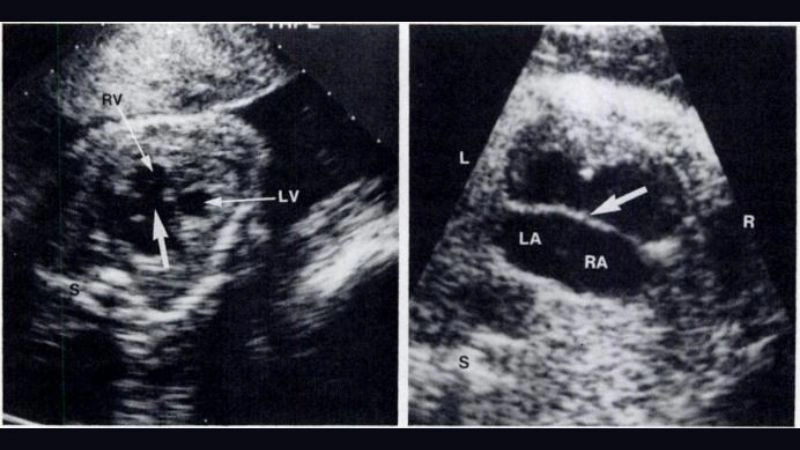

Images Visual Examples Of Atrioventricular Canal Defect (Endocardial Cushion Defect)

Atrioventricular Canal Defect is a congenital heart disease where the walls separating chambers do not form properly, leading to mixing of blood and heart inefficiency.